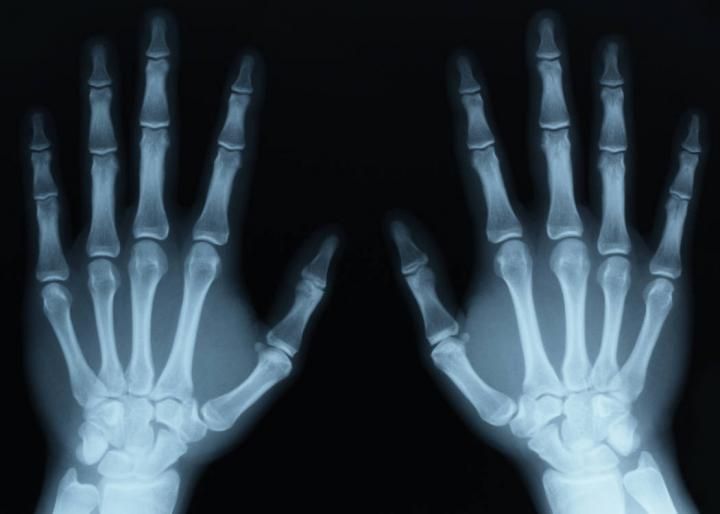

The Use Of X-Ray In The Medical World Explained

Who decides whether you will need to get an X Ray? Well, when every time a doctor or a medical expert can’t figure out the cause of pain or discomfort through physical examination; he/she will recommend you to take this test. Another advantage of it — you don’t need to prepare for it in advance...